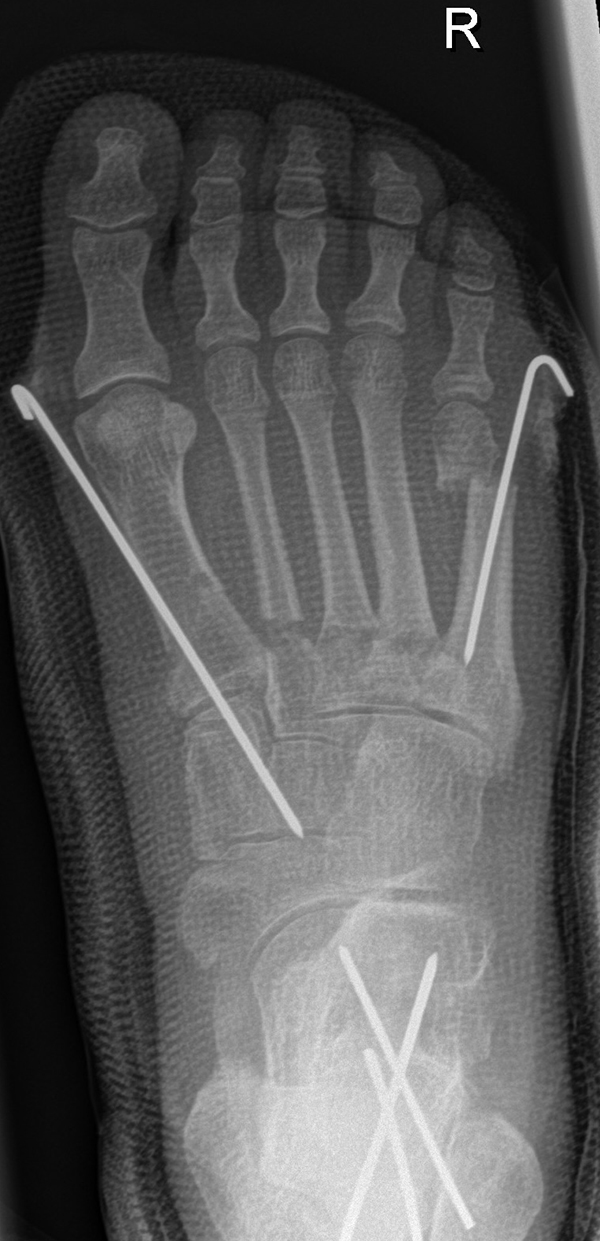

Zusätzlich schränken Wachstumsfugen die Wahl der Osteosynthese ein. Eine die Fuge kreuzende Osteosynthese ist ausschließlich mit Kirschner-Drähten möglich (Abb. 3).

Abb. 3 a-j: Beispiel einer Calcaneusverschiebeosteotomie mit offenen Wachstumsfugen und der entsprechenden Osteosynthese mit Kirschner Drähten. Lokalisation der Osteotomie (a), Lage der Fräse (b-d), Drahtlage mehrere Ansichten (e-h), Heilung der Osteotomie 4 Wochen postoperativ und Entfernung der Drähte (i-j).

Zum Lesen der Bildbeschreibung und zur Vollansicht bitte die Bilder anklicken. Bilder: A. Helmers.

Calcaneus-Osteotomie

Die minimalinvasive Calcaneusverschiebeosteotomie bietet eindeutige Vorteile gegenüber dem offenen Verfahren, sodass wir bei Kindern und Jugendlichen nahezu keine offene Verschiebeosteotomie mehr durchführen. Am Calcaneus liegt die offene Wachstumsfuge dorsal. Bei der Durchführung müssen Schenkel der V-förmigen Osteotomie daher etwas steiler angelegt werden, in einem stumpfen Winkel (siehe Abb. 3 a-j). Für die Osteotomie liegen unsere Patienten auf dem Rücken und der BV wird für die exakte Seitaufnahme eingestellt. Der Fuß lagert auf einem hohen OP-Kissen und die Osteotomie kann bequem mit einem langen Kirschner-Draht und einem sterilen Stift angezeichnet werden (Abb. 15).

Damit lässt sich im Verlauf Röntgenstrahlung für die jungen Patienten vermeiden und die minimalinvasive Osteotomie kann sicher durchgeführt werden. Anschließend erfolgt die Verschiebung oder Impaktion. Ist ein Gleiten nach plantar oder cranial des distalen Fragmentes erwünscht, wird die Osteotomie schräg ohne V-Form entweder verlängernd oder verkürzend durchgeführt (Abb. 16).

Durch den knöchernen Defekt der Fräse gelingt die Verschiebung bei der minimalinvasiven Osteotomie im Fall von strukturell festen Klumpfüßen mit starkem Zug der verkürzten Achillessehne oder bei einer fixierenden spastischen Grunderkrankung einfacher gegenüber dem offen Verfahren. Ein weiteres Plus bei hyperaktiven Weichteilen ist die Vermeidung der ungewollten Cranialisierung des dorsalen Fragmentes durch die V-förmige Osteotomie (Abb. 16).

Die minimalinvasive Calcaneusverschiebeosoteotomie kommt somit in der Versorgung von kindlichen und jugendlichen Fußdeformitäten in einem weiten Erkrankungsspektrum zum Einsatz (Abb. 16):